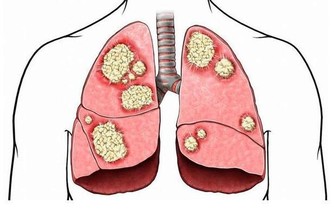

6.食物來不及消化,產生有毒物質誘發腸癌

晚餐吃得太晚,來不及完全消化,殘餘的蛋白質在腸道細菌的作用下會產生有毒的物質,又由於睡眠時腸道的蠕動很慢,使這些毒素在腸道內停留時間延長,在其長期刺激下,可誘發慢性腸炎及腸癌。

7.加速血管老化,誘發冠心病

晚飯吃得太晚,肝臟會將多餘的熱能轉變成膽固醇,致使血中膽固醇水平增高,並逐漸堆積在血管壁上,造成動脈硬化,至一定程度,就會發展成冠心病。同時,血液集中於腸胃道幫助消化吸收而使心臟供血相對不足,導致心絞痛發作。

8.胰島細胞勞損,導致糖尿病

晚餐吃得太晚,會因刺激胰島素持續大量分泌,致使分泌胰島素的B 細胞負擔過重,如果是長期的持續超負荷分泌,特別是中老年人則會因B細胞功能衰竭而誘發糖尿病。